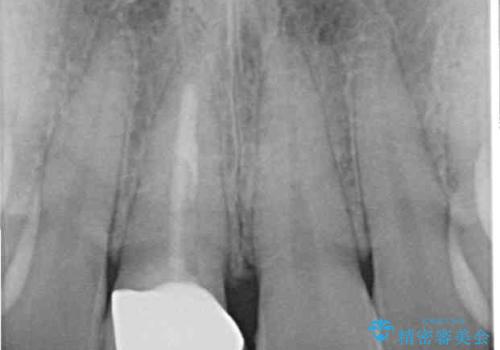

- 近医にて被せた前歯のクラウンの色の違いを気にして来院された患者様です。

オーダーメイドのオールセラミッククラウンにて補綴することとしました。

元々すきっ歯であったため、隙間を全て埋めると左右で大きさがアンバランスとなることが懸念されました。

違和感のない程度に隙間を小さくして、自然な見た目に仕上げました。